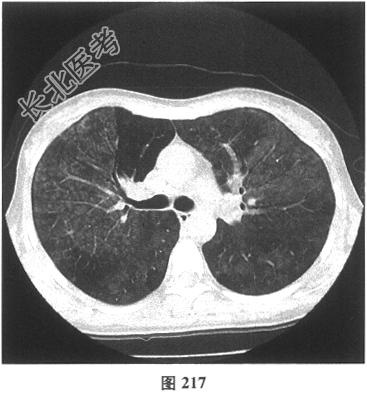

- [材料题] 患者女性,职员,43岁,以"反复咳嗽2个月余,咳痰、活动后气喘2周"就诊。体检:双肺未闻及干湿性啰音。既往无吸烟史。肺部CT见图216~图219。

- 多项选择题2.[提示]患者发病前3个月曾装修过房屋。目前考虑患者最可能的诊断为( )